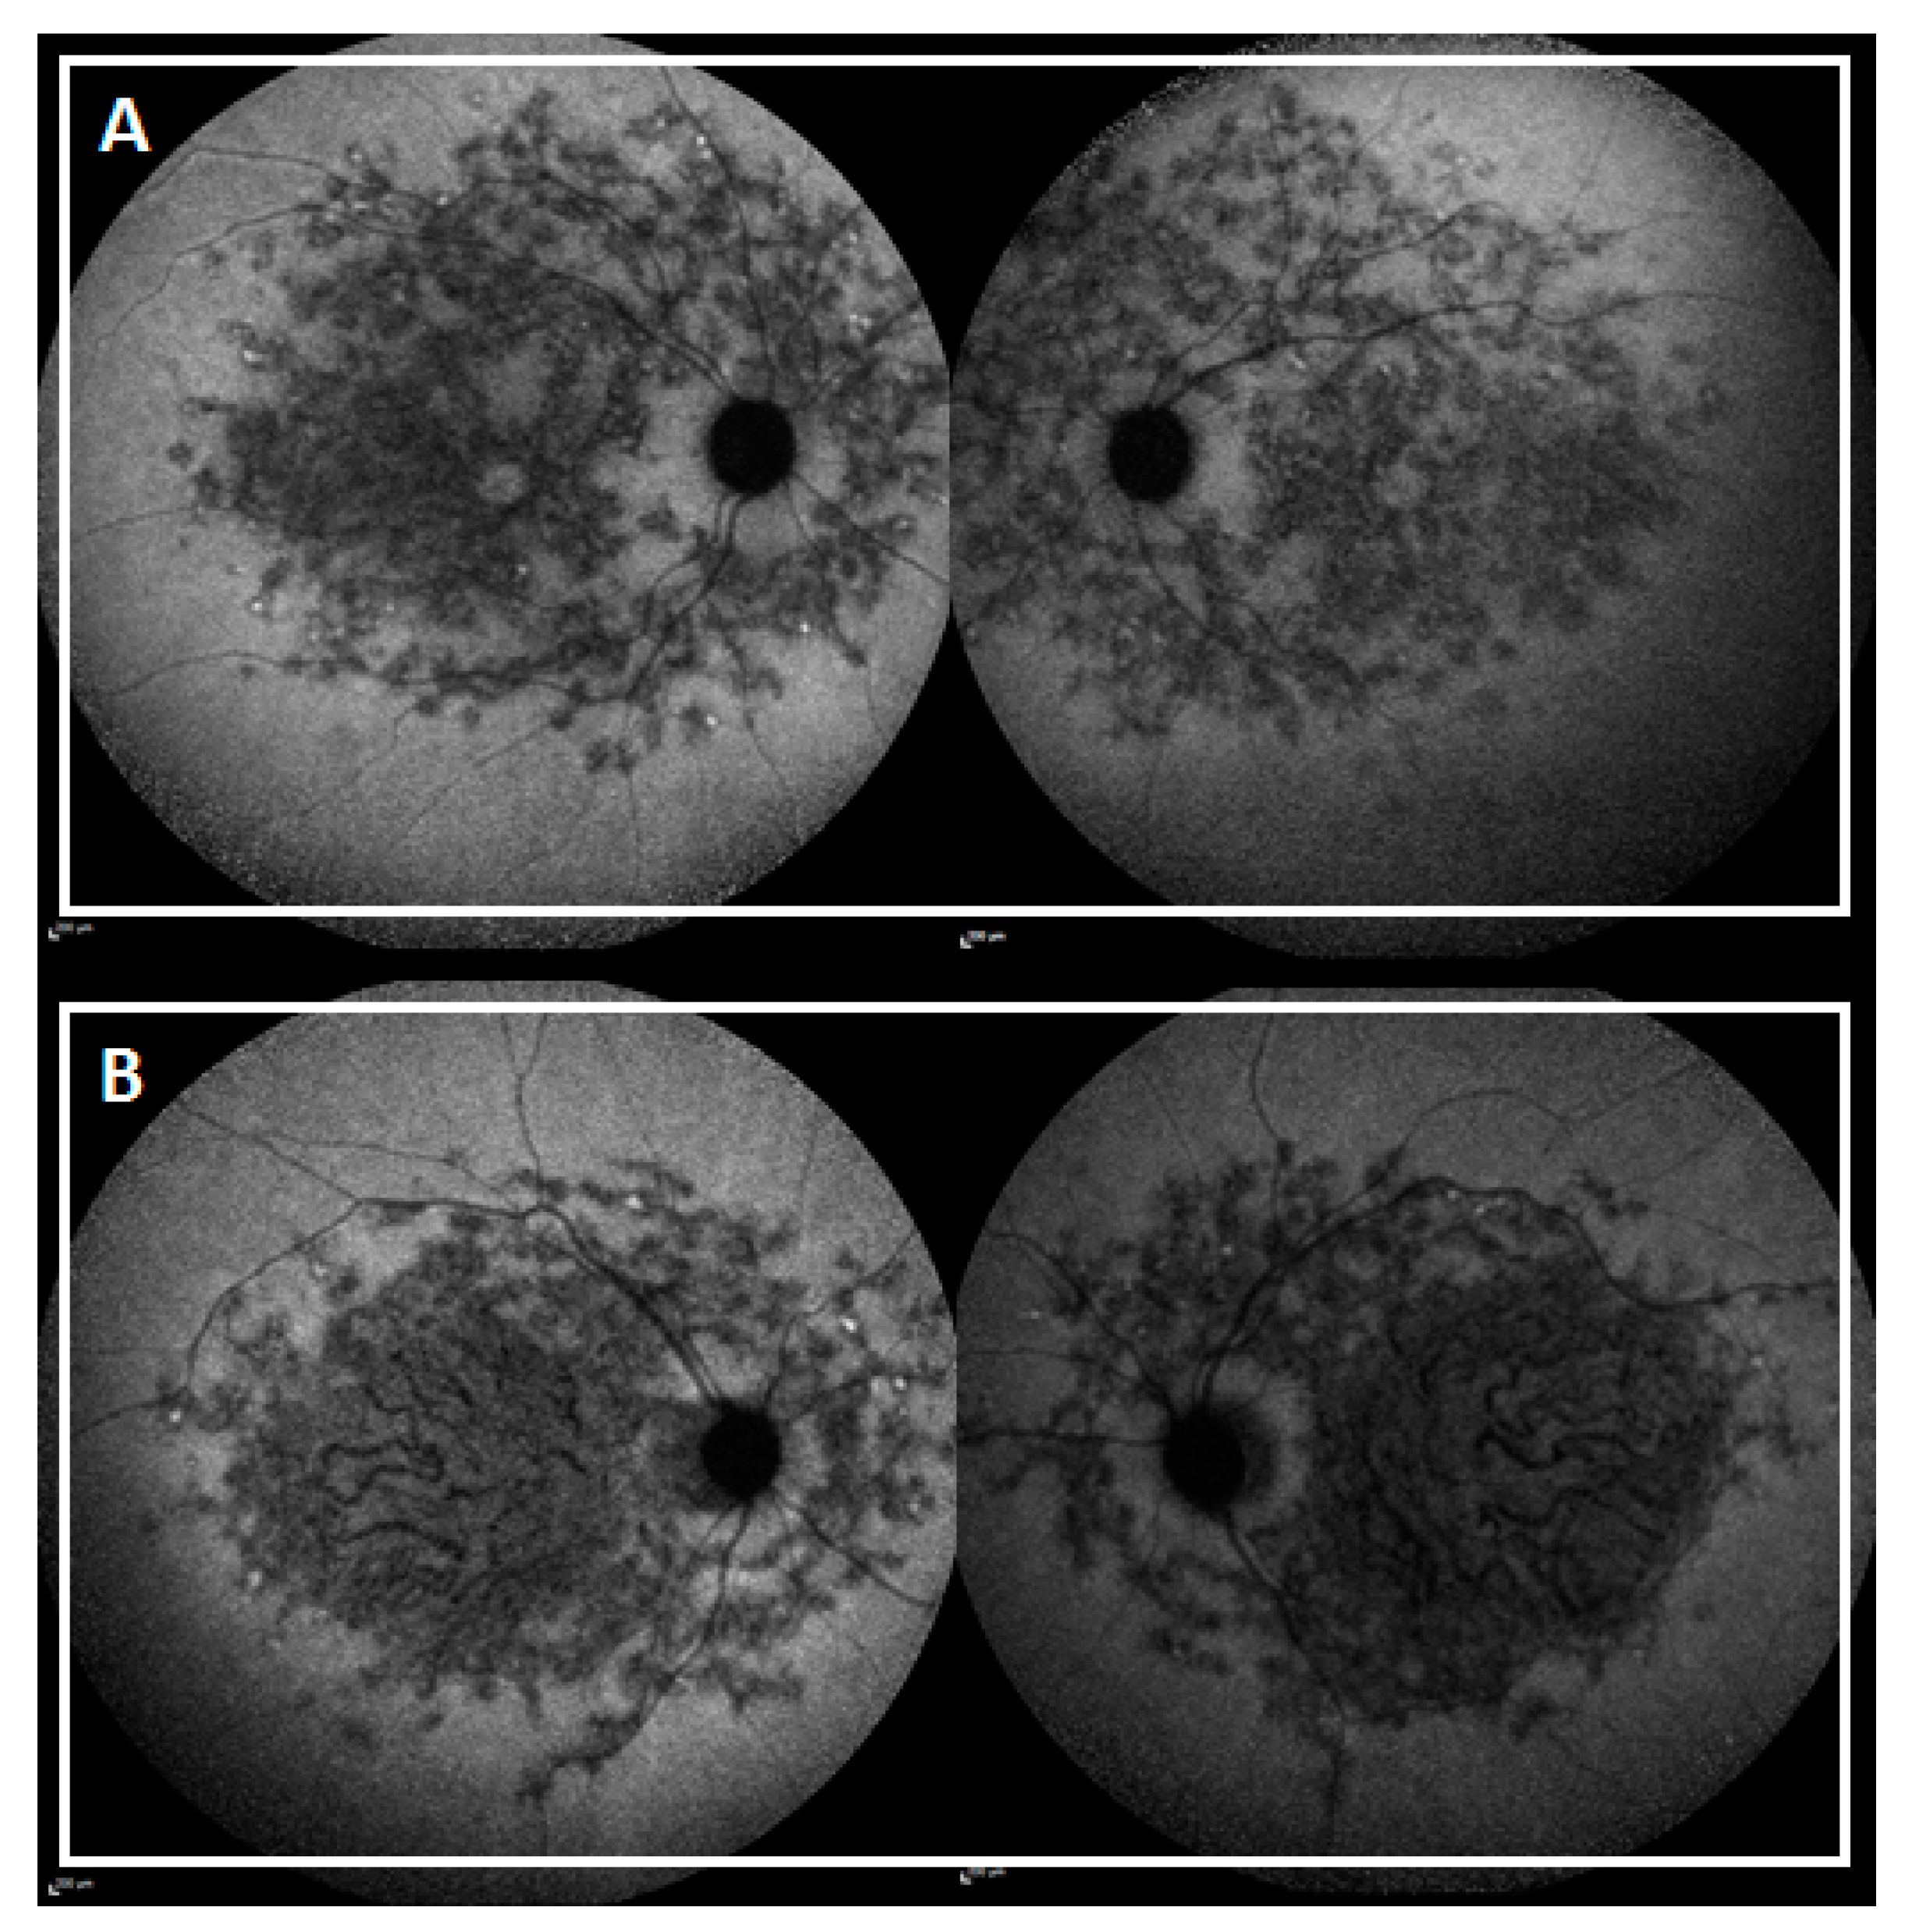

| SW-AF and NIR-AF | Group 1 | Central lesion with jagged border | Duncker et al., 2014 [55] |

| Group 2 | Lesion with extensive fundus changes | ||

| Group 3 | Central lesion with smooth border and hyperautofluorescent SW-AF and NIR-AF ring | ||

| Group 4 | Central lesion with smooth border and no hyperautofluorescent NIR-AF ring | ||

| Group 5 | Discrete central lesions better visualized in NIR-AF images | ||

| Peripapillary area preserved | No alterations within an eccentricity of 0.6 mm from the optic disc | Cideciyan et al., 2005 [56] | |

| Flecks in the peripapillary area | Presence of flecks within an eccentricity of 0.6 mm from the optic disc | ||

| Peripapillary area not preserved | Absence of EZ band and/or EPR atrophy within an eccentricity of 0.6 mm from the optic disc | ||